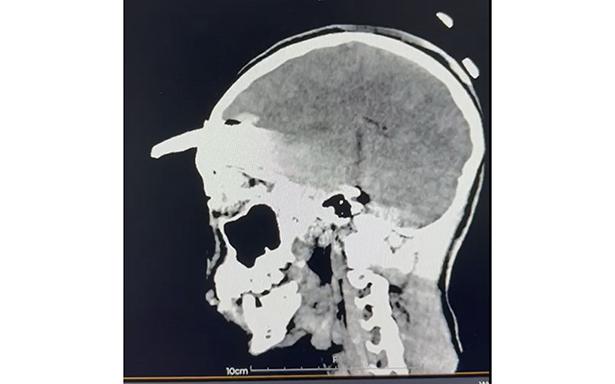

Se dio a conocer que mediante una compleja cirugía, se logró retirar la herramienta agrícola -coa- de aproximadamente 30 centímetros incrustada en el cráneo de un adolescente de 15 años, procedimiento que permitió salvarle la vida.

Tras confirmarse un traumatismo craneoencefálico severo, se realizaron estudios inmediatos que determinaron la profundidad y ubicación del objeto.

Los estudios de imagen permitieron ubicar con precisión el objeto, mientras que el menor recibía tratamiento con antibióticos de amplio espectro para prevenir infecciones asociadas con el instrumento metálico.

Después de un análisis minucioso y una planeación quirúrgica, el doctor Ornelas González dirigió un procedimiento de cuatro horas que permitió retirar exitosamente el machete curvo sin afectar tejido cerebral.